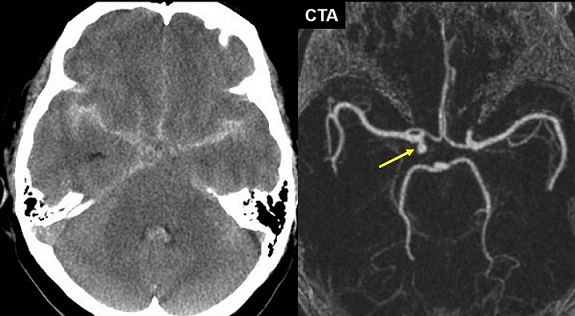

【112-1 醫學(四) 第75題】60歲女性因頭痛到急診就醫,根據所附頭部電腦斷層(CT)與電腦斷層血管造影(CTA)影像判斷,下列敘述何者正確?